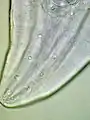

These are all pictures from a single Gongylonema pulchrum male extracted from a man in France.[1]

Head